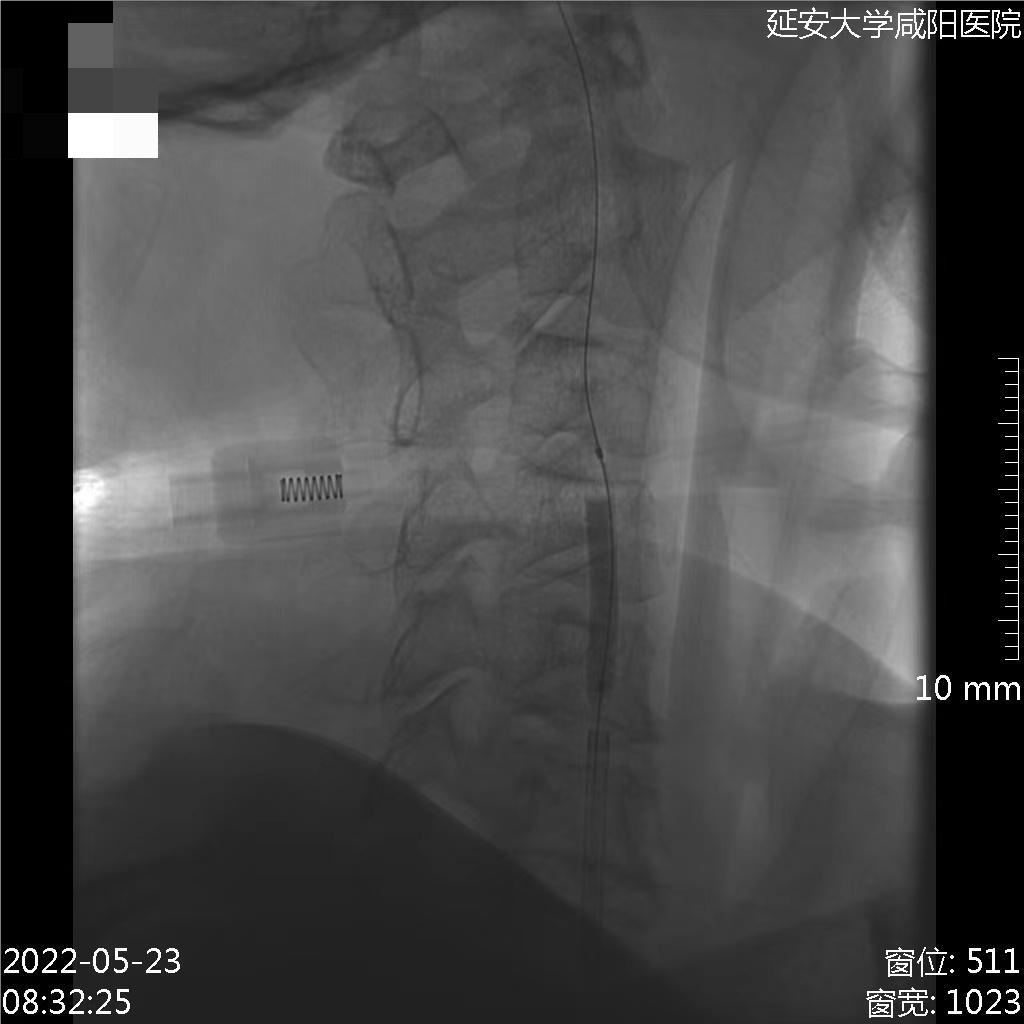

术后情况

呼之能应,言语欠清,四肢可见肢体活动。

查体:神志嗜睡状,言语欠清,双瞳等大形圆直径1.5mm,光反射迟钝,双眼可见眼球活动,伸舌居中,四肢肌力2+级,四肢肌张力不高,双侧病理征阳性。NIHSS评分15分(意识1分+意识水平提问1分+意识水平指令1分+凝视1分+视野1分+面瘫0分+上下肢运动6分+感觉2分+语言1分+构音障碍1分)。

术后即刻、14小时与18小时复查头颅CT

病历夹什么径技·第152期|串联营病历夹:川陕大营_https://www.jmylbn.com_新闻资讯_第29张

病历夹什么径技·第152期|串联营病历夹:川陕大营_https://www.jmylbn.com_新闻资讯_第30张

病历夹什么径技·第152期|串联营病历夹:川陕大营_https://www.jmylbn.com_新闻资讯_第31张

病历夹什么径技·第152期|串联营病历夹:川陕大营_https://www.jmylbn.com_新闻资讯_第32张

<<滑动查看下一张图片>>

术后14小时小脑梗死灶水肿,四脑室显影不佳,是否需要急诊后颅去骨瓣减压?

认为去骨瓣更好,但该患者进行去骨瓣选择时家属选择不去骨瓣,结果发现患者预后不佳。